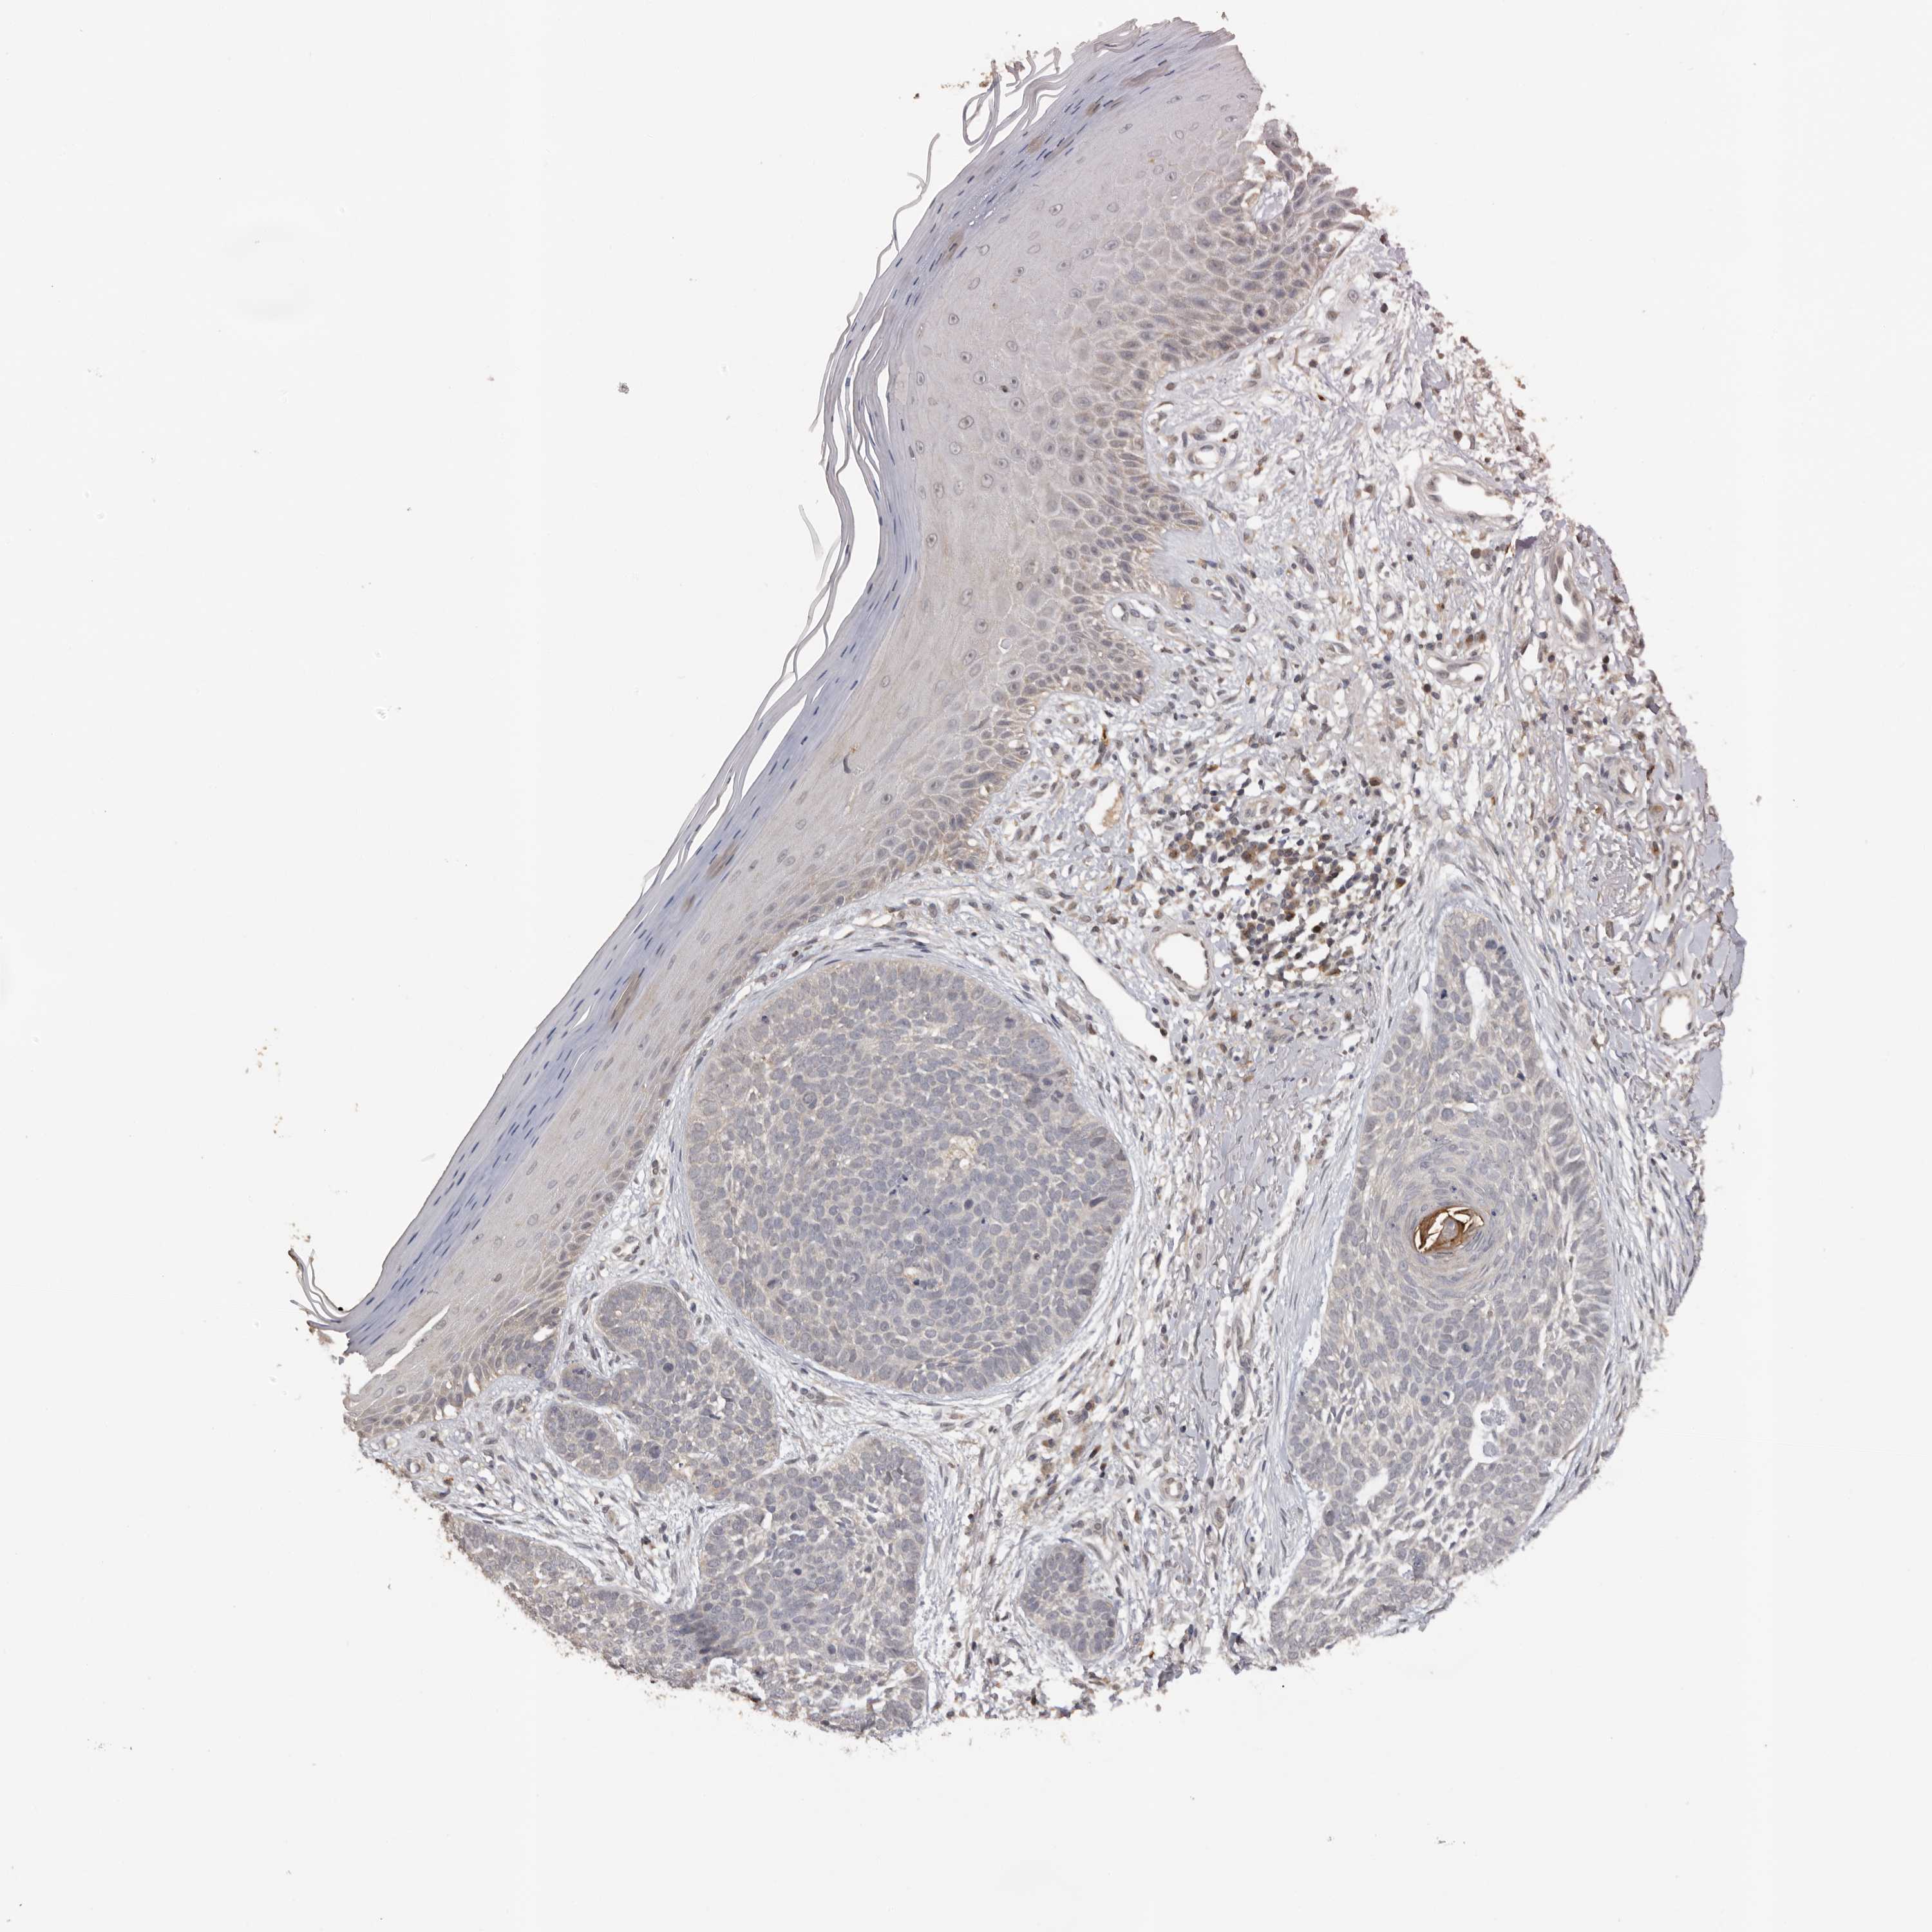

Basal cell and squamous cell cancer

SKIN CANCER - Protein expressioni

A mouse-over function shows sample information and annotation data. Click on an image to view it in a full screen mode. Samples can be filtered based on level of antibody staining by selecting one or several of the following categories: high, medium, low and not detected. The assay and annotation is described here.

Antibody stainingi

Antibody staining in the annotated cell types in the current human tissue is reported as not detected, low, medium, or high, based on conventional immunohistochemistry profiling in selected tissues. This score is based on the combination of the staining intensity and fraction of stained cells.

Each image is clickable and will lead to virtual microscopy that enables deeper exploration of all samples and also displays staining intensity scores, fraction scores and subcellular localization as well as patient and tissue information for each sample.

Antibody HPA023081

Antibody HPA023103

Antibody HPA024795

Staining

High

Medium

Low

Not detected

Intensity

Strong

Moderate

Weak

Negative

Quantity

>75%

75%-25%

<25%

None

Location

Nuclear

Cytoplasmic/membranous

Cytoplasmic/membranous,nuclear

Squamous cell carcinoma, metastatic, NOS